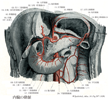

十二指腸【じゅうにしちょう】 The ca. 25-30 cm long segment of the small intestine between the pylorus and duodenojejunal flexure.(十二指腸は胃の幽門から十二指腸空腸曲まで約25cmの腸管。十二指腸Duodenumは12で、intestinum duodenum digitorumの意味。長さが指を12本横にならべた幅に等しいことによる。第1腰椎の椎体右縁の前方ではじまり、C字状に屈曲して膵臓の頭を取り囲む。腸間膜を欠き、後腹膜臓器の一つであり、胆管、膵管が開口するなど他の小腸とは異なる。十二指腸には4部が区別される。上部は幽門につづく5cmの長さの部で、上背外側へはしる。最初の2.5cmは可動性。上縁には小綱が付着する。上十二指腸曲において、ほぼ下方へ屈曲し、下行部(約8cm)へ移行する。その半ばで後内側壁に一条の十二指腸ヒダがり、その下端に大十二指腸乳頭が隆起し、ここに総胆管と膵管が共通に開口する。その上方2~3cmの部に小十二指腸乳頭があることが多く、副膵管の開口をみる。下行部は下十二指腸曲で左方へ屈曲し、水平部(下部、約8cm)へ移行し、第3腰椎体左縁に達し、左上方へ屈曲し、上行部へつづく。この部は約5cm走行したのち、第2腰椎の左方で急に前方に曲がり空腸へ移行する。この部を十二指腸空腸曲という。この曲がりは、横隔膜直下の後大動脈壁から下降する十二指腸提筋で固定されている。十二指腸の前半、ほぼ大小十二指腸乳頭までには、よく発達した十二指腸腺がある。複合管状胞状腺で、分泌物は粘液性でアルカリ性を示すことから胃酸から粘膜を保護するのではないかといわれる。)